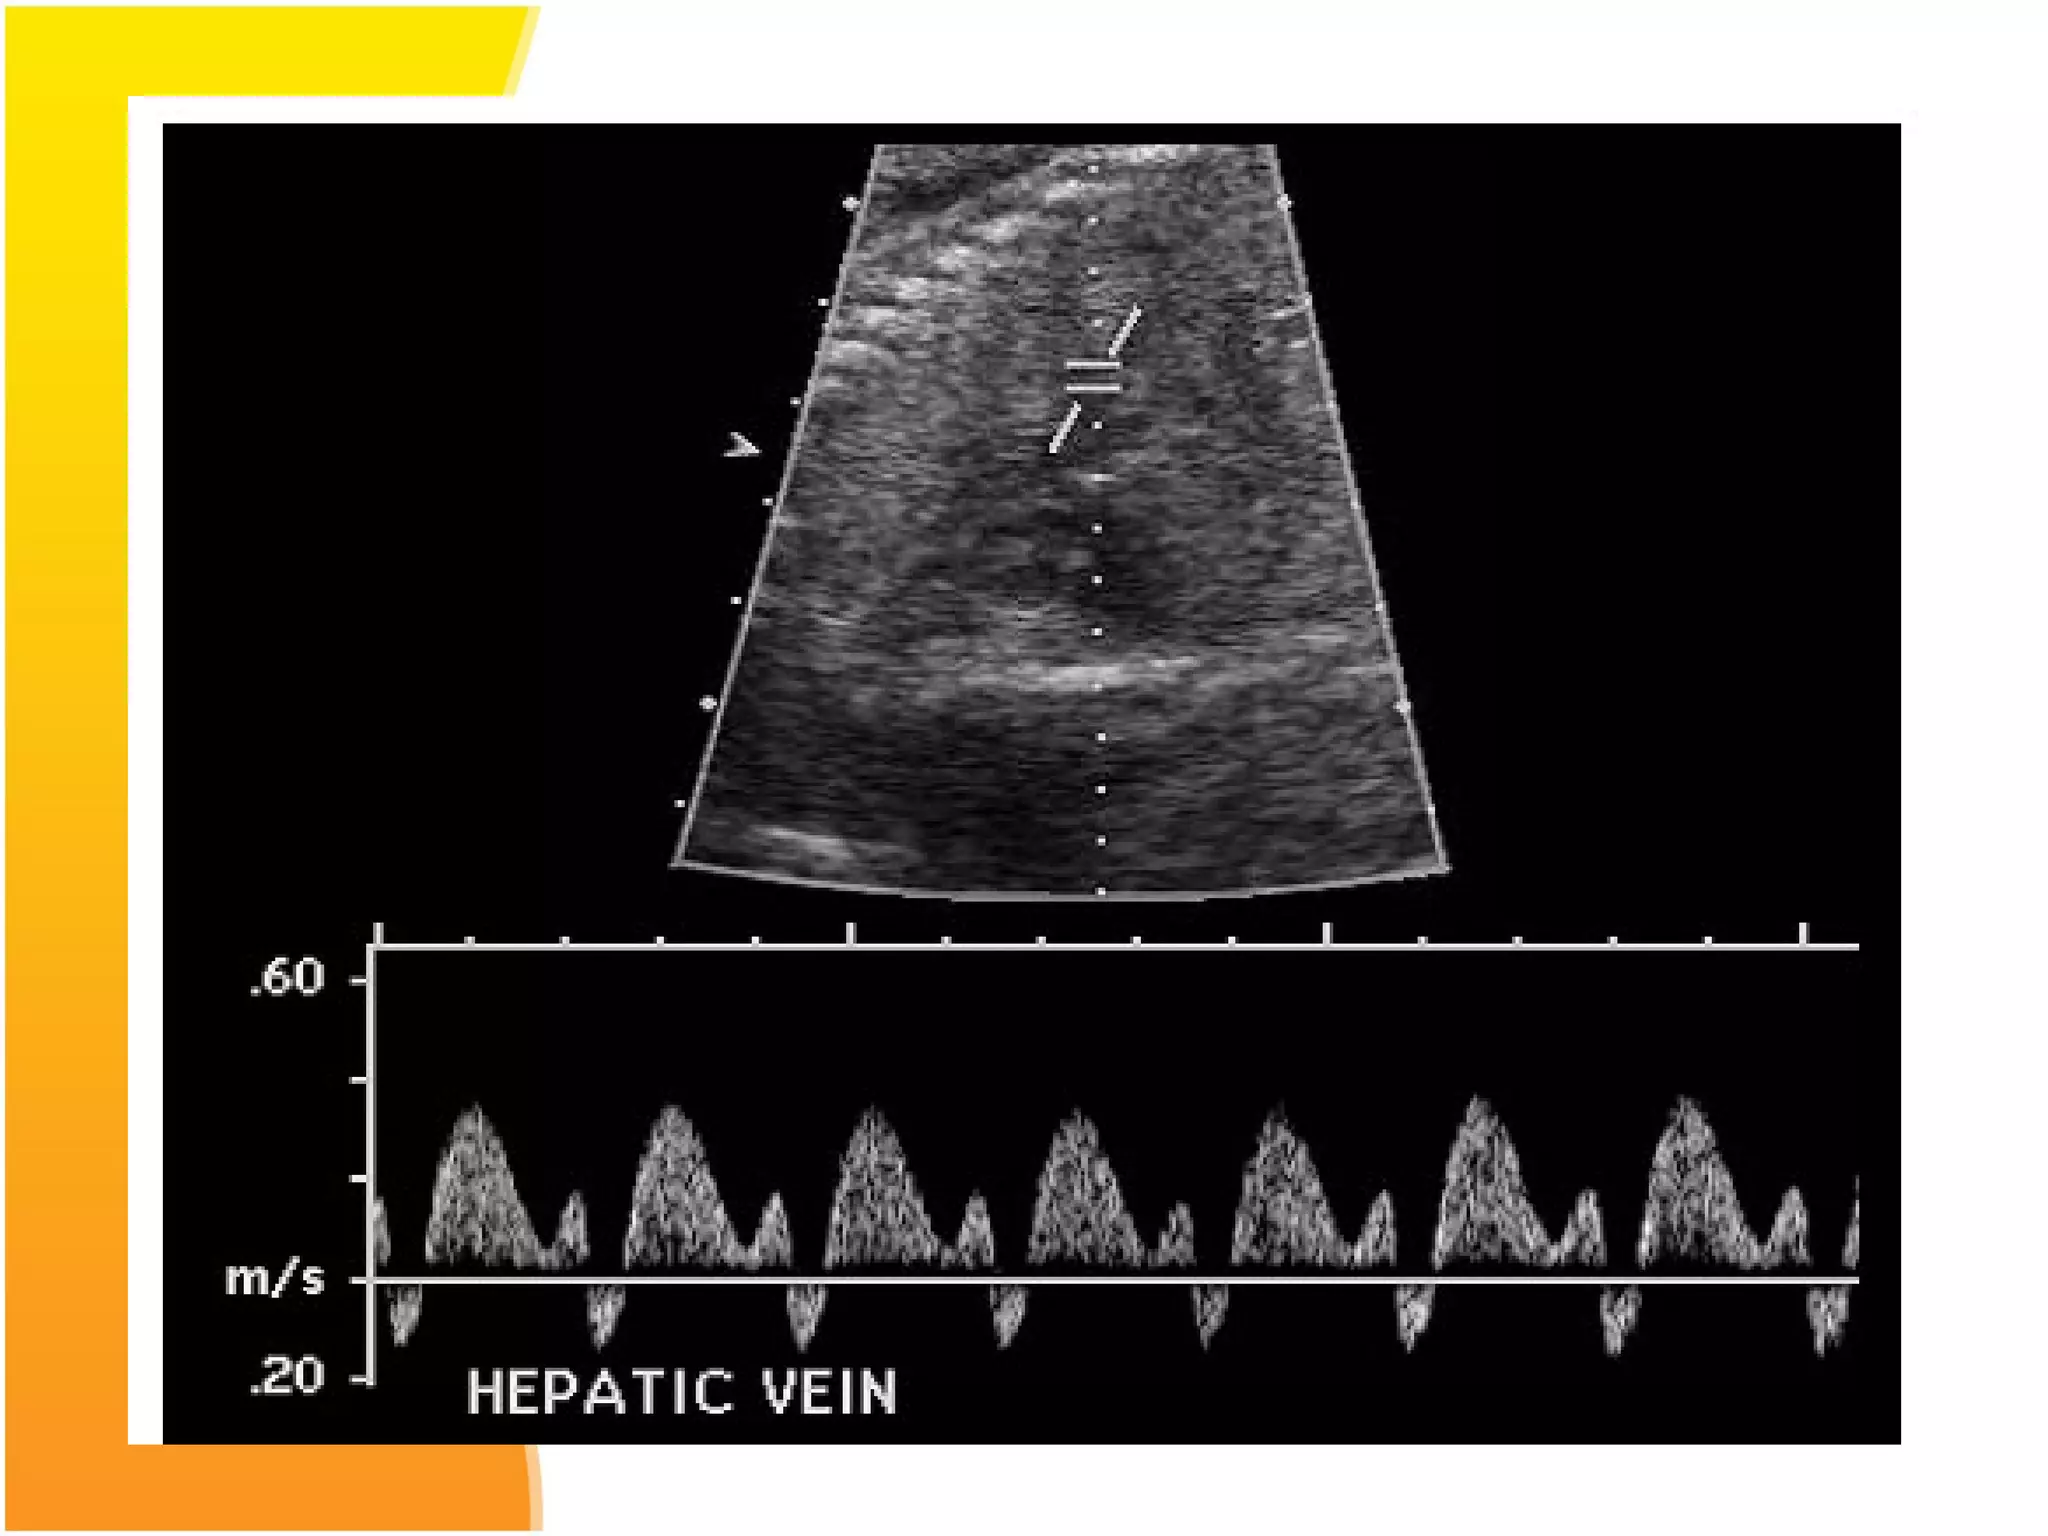

 Ductus venosus doppler: Perinatal mortality in

growth restricted fetuses has been found to be

significantly worse when abnormalities in fetal

venous circulation are detected.

In the normal fetus, flow in the ductus venosus is

forwards , moving towards the heart during entire

cardiac cycle.

When circulatory compensation of the fetus fails, the

ductus venosus waveform shows absent or reverse

blood flow during atrial conraction. Perinatal mortality

being 63-100%.

Therefore it is recommended that fetus should be

delivered before the development of absent of reversed

blood flow of DV.

: Representation of fetal umbilical and hepatic

venous system. The arrows indicate the direction

of flow.

FO, foramen ovale; RA, right atrium; DV, ductus

venous; UV, umbilical vein; HV, hepatic veins; IVC, inferior vena

cava; PS, portal sinus; LPV, left portal vein; RPV, right portal

vein; EPV, extrahepatic portal vein; GB, gallbladder

 Ductus venosusdoppler: Perinatal mortality in growth restricted fetuses has been found to be significantly worse when abnormalities in fetal venous circulation are detected. In the normal fetus, flow in the ductus venosus is forwards , moving towards the heart during entire cardiac cycle. When circulatory compensation of the fetus fails, the ductus venosus waveform shows absent or reverse blood flow during atrial conraction. Perinatal mortality being 63-100%. Therefore it is recommended that fetus should be delivered before the development of absent of reversed blood flow of DV.

: Representation offetal umbilical and hepatic venous system. The arrows indicate the direction of flow. FO, foramen ovale; RA, right atrium; DV, ductus venous; UV, umbilical vein; HV, hepatic veins; IVC, inferior vena cava; PS, portal sinus; LPV, left portal vein; RPV, right portal vein; EPV, extrahepatic portal vein; GB, gallbladder